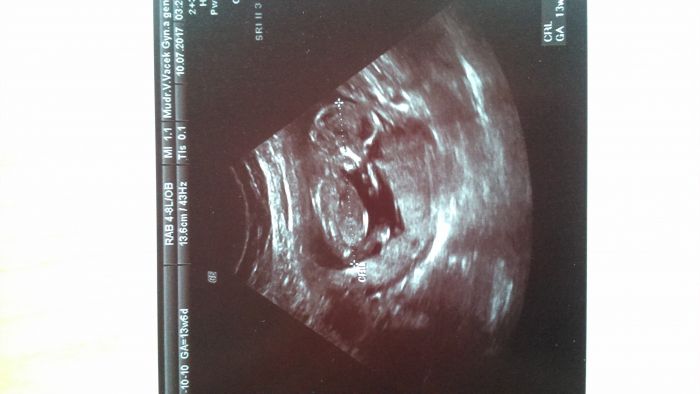

Giglesko nádhera! U máš tip, jestli to bude kluk nebo holka? Já jsem třeba od začátku tak nějak cítila, že to bude kluk..a jména už vybíráte?